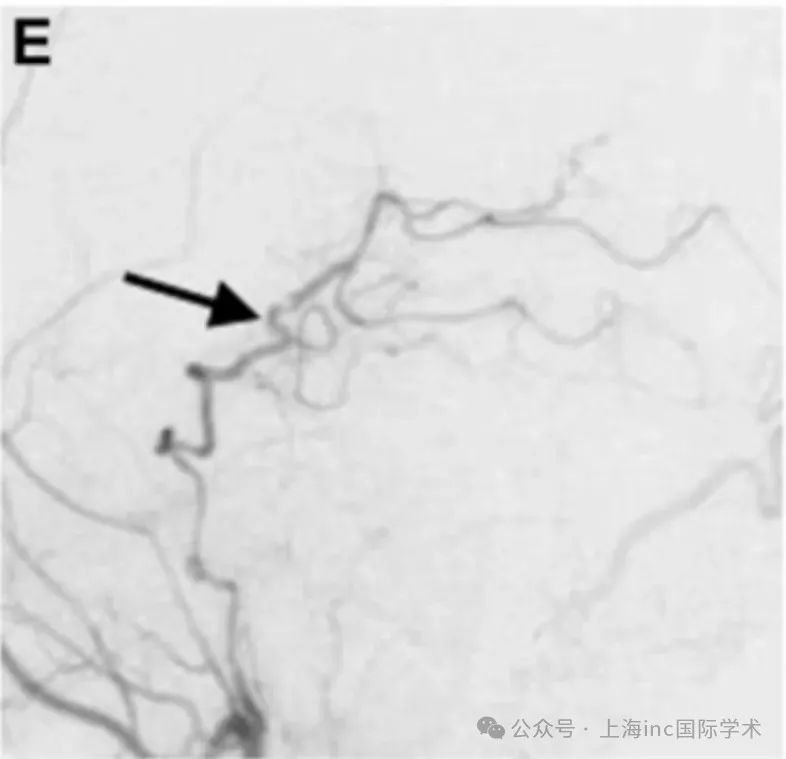

术后1周,血管造影显示,通过旁路到达左侧 PCA 区域的血流良好,并且动脉瘤完全被排除。

在1年随访中,患者改良Rankin评分为 0.搭桥术仍然有效。